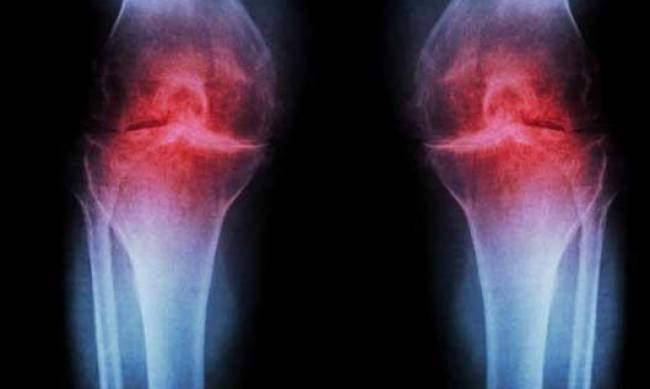

У молодому віці ви бігали і були бадьорі, як огірочок. Але ось після 30 років розумієте, що молодість безповоротно проходить: все болить, хрумтить, погано розгинаються суглоби. Знайомтеся – його величність артроз. Чому виникає це захворювання і чи можна від нього захиститися, розповідаємо в нашому матеріалі.

Артроз являє собою захворювання суглобів. Воно одне з найпоширеніших по всьому світу. Не можна сказати, що артроз надмірно небезпечний. Однак може суттєво знизити якість життя, тому що виникають хронічні болі і порушення рухливості суглобів. Все це при неправильному лікуванні (або відсутності такого) може призвести до інвалідного візка.